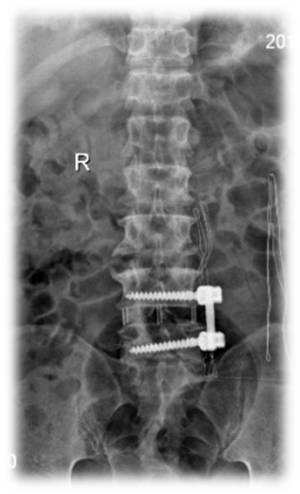

术后 图片1